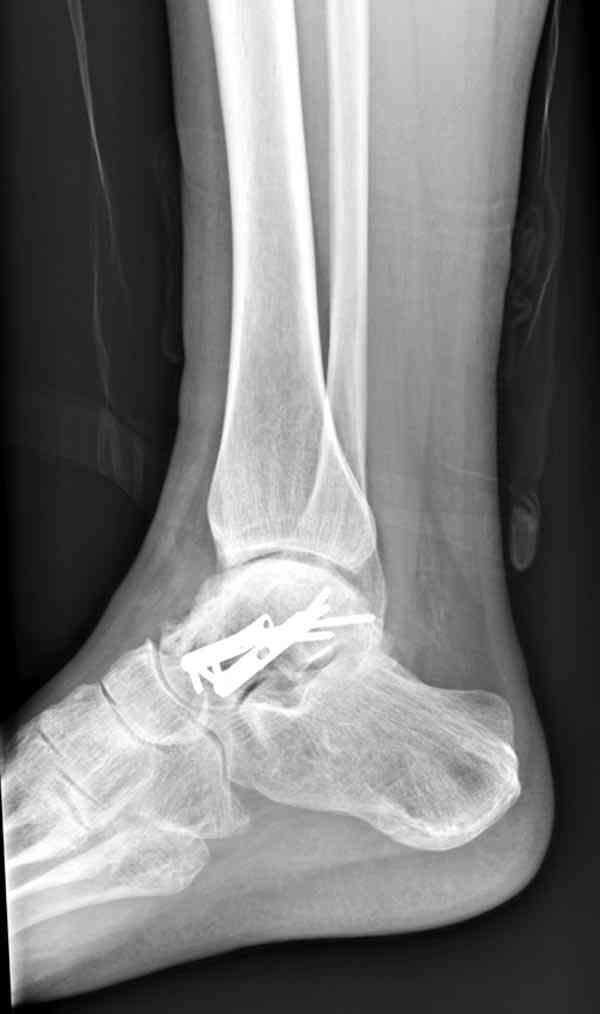

Случай с множественным оскольчатым переломом тарана оперированный из двойного доступа.

Через 2 мес.:

И второй случай из недавней ташкентской практики, (извините за качество ренгенограммы и только в одной проекции) случай падения с высоты (кстати моего друга - известного киноактера) - открытый

смещенный перелом тарана, с переломом переднего края дистального эпиметафиза большеберцовой кости.

При поступлении в приемной сделана первичная обработка с ушиванием открытой латеральной раны и вытяжением за пятку.

Из-за отсутствия времени пришлось оперировать на второе утро, из материала, что имеем на месте, фиксирован двумя шурупами, а третий-это контур сломанного жойстика в 4 мм. На дистальный медиальный конец тибиа antiglide 3.5 мм пластина. Через пару дней выписан и несмотря на предупреждение, самостоятельно начал нагрузку в 4 недели, время не ждет, снимается в боевике в Росийской Федерации.